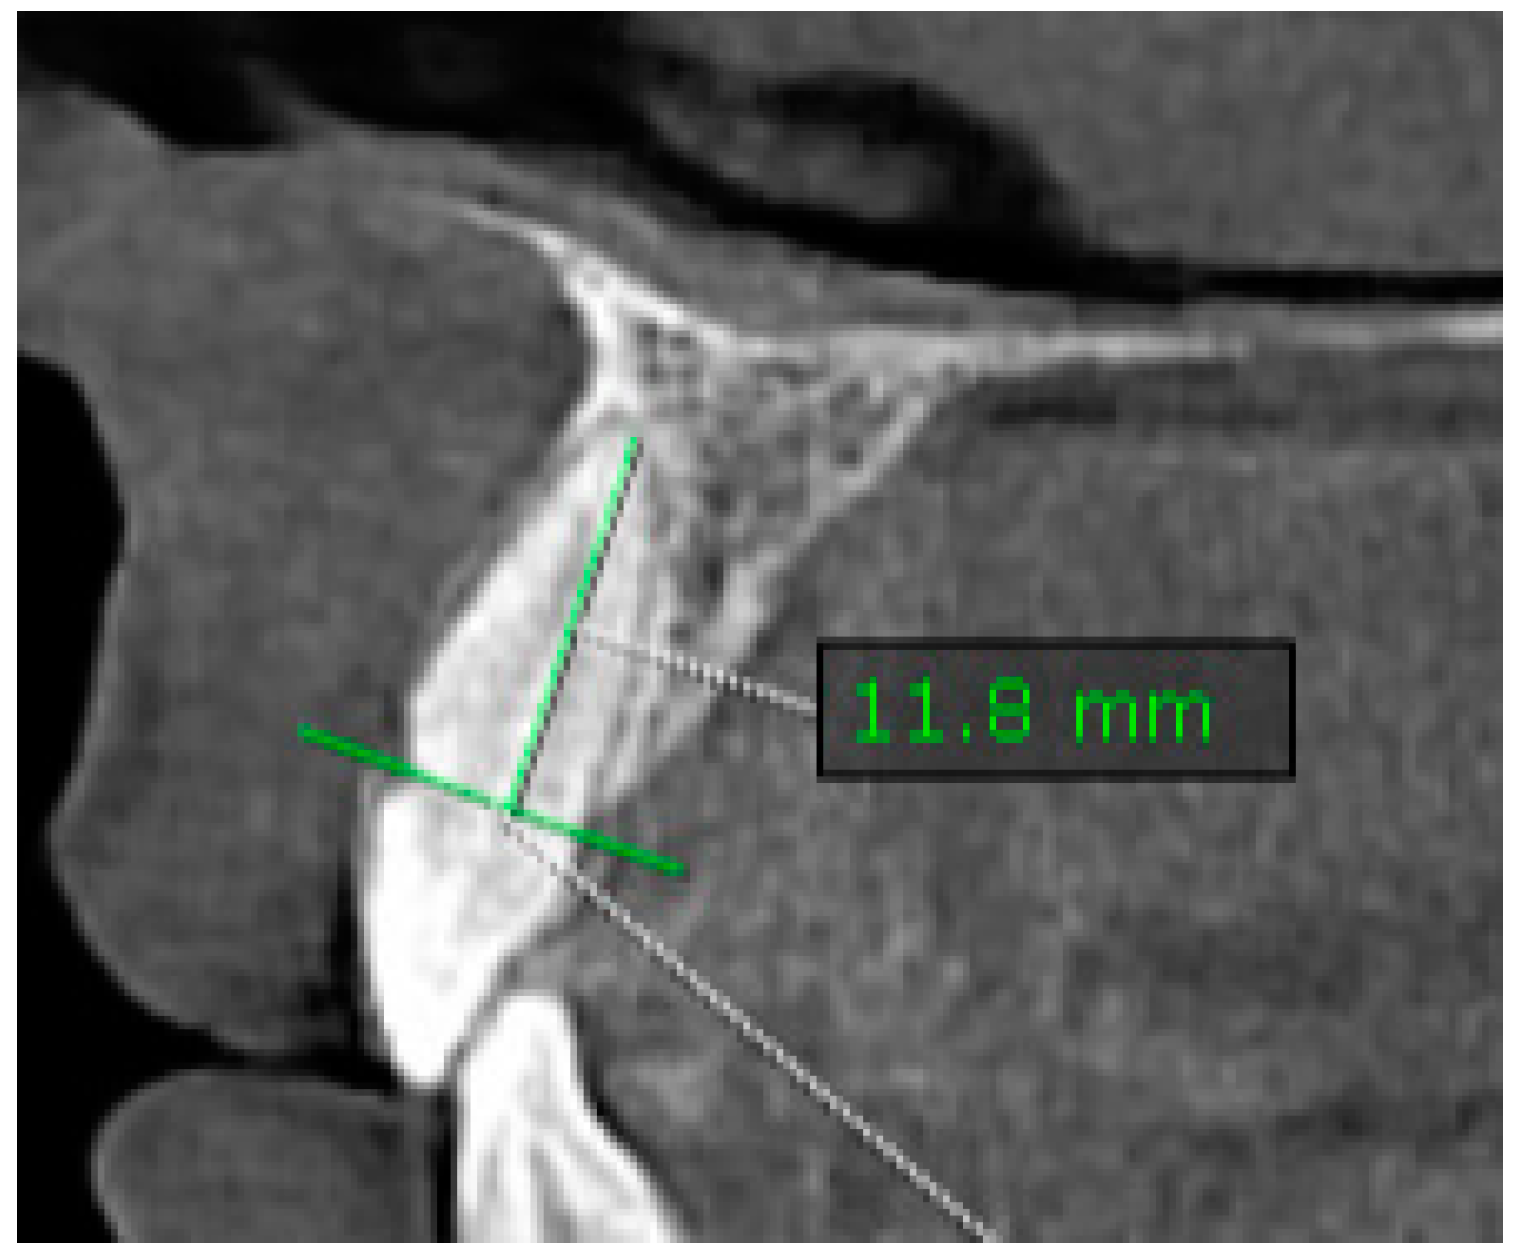

2.1.3. Assessment of Root Length (RL)

- Measurements were taken in the sagittal plane at the CIs of maxillary and mandibular teeth (Figure 2).